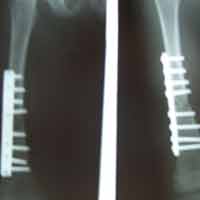

Case:14 Periprosthetic Fracture

60 years old patient with total knee replacement on left knee presented with open grade 1 injury. Debridement & slab given on emergency bases. Fixation with plate & screws done. Union was seen after 6 months.

Pre-Op AP

Pre-Op Lat.

Immdiate Post-op

1 and half months Post-op

2 and half months Post-op

3 and half months Post-op

4 and half months Lateral

6 Years Follow-Up